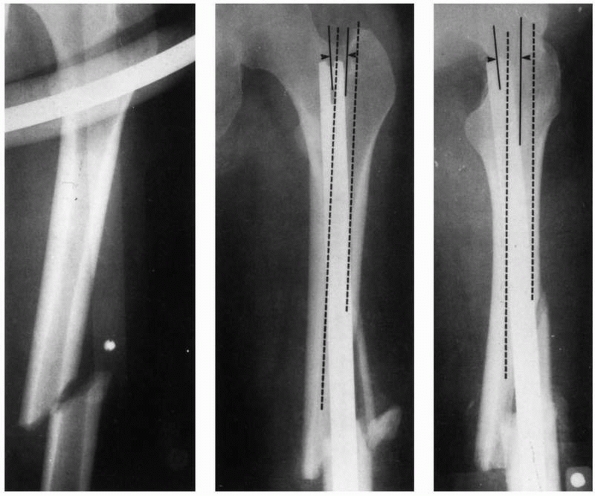

can lead to difficulties because the femur has a significant anterior

curvature,169 shown in Figure 1-40.

Current femoral nails have radii of curvature that range from 186 to

300 cm, compared with the average for a large sample of femora, which

was 120 +/- 36 cm. Therefore, current femoral nails are considerably

straighter than the femora they are inserted into.49

The rod, which also has a curved shape to accommodate the femoral bow,

must conform to the curvature of the femur as insertion progresses.

Placing a rod, which is essentially a steel curved spring, down the

femoral canal causes the rod to bend, because the femur is generally

much stiffer than the rod, Figure 1-41. In fact, the nail must conform not only to an anterior-posterior

bow but also canal curvature medially and laterally.51 Figure 1-42

demonstrates that rod contact with the internal surfaces of the femur

generates forces which resist insertion. These rodfemur contact forces,

directed perpendicular to the surface of the medullary canal cause the

femur to expand and will result in splitting if they become too large.80

during insertion and the resulting internal forces acting within the

femur are the proximal starting hole position, the length of the

proximal fragment, the initial curvature of the IM rod compared with

the curvature of the femur, and the rod bending stiffness. Stiffnesses

of rods can vary considerably.131 Figure 1-42 demonstrates examples in which rod proximal starting hole position resulted in femoral splitting during rod insertion.80 Some newer IM nails employ a valgus bend to be used with a femoral trochanteric entry portal.120